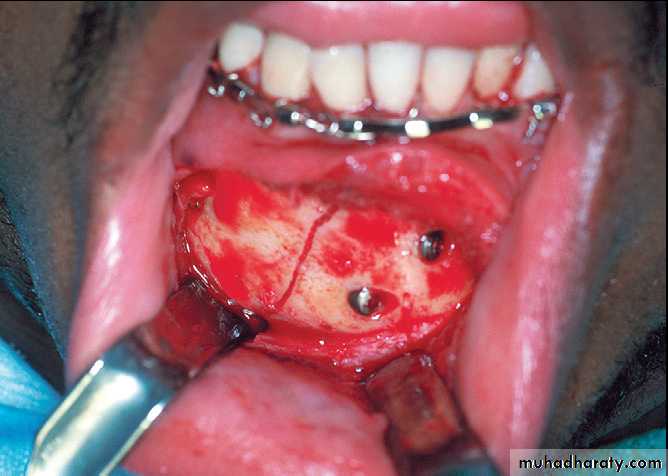

There have been several methods to restore occlusion to edentulous patients which include Gunning’s splint and the application of an arch bar into the denture. Unfortunately, these 2 techniques are very time consuming and require laboratory procedures to apply these to the dentures.Skeletal anchorage system (SAS), which is a simple and relatively easy method to conduct.

The SAS provides anchorage to both the bone and the maxillo-mandibular fixation and also can be performed without severe modification of the patient’s denture.

After making holes in the dentures, the dentures are adapted to the jaws of the patient. The SAS screws can be placed into the holes providing denture stability and the anchorage for the intermaxillary fixation. Once the fracture treatments are completed the patients may continue to use their dentures, which only require minimal repairs after the procedure.